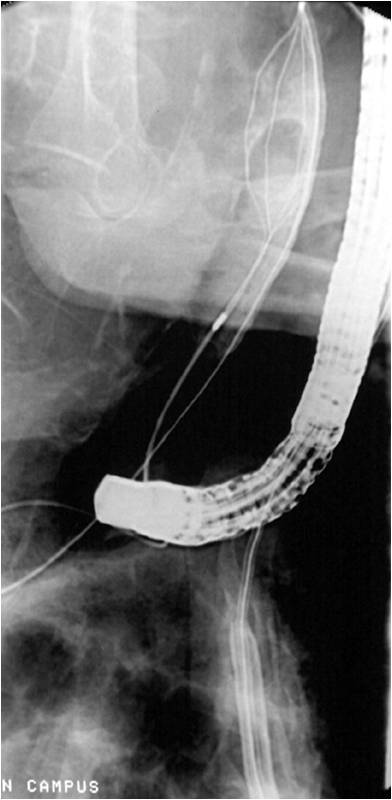

| תצלום 16.8: ניקוז דרכי המרה. תמונה ימנית בעזרת צנתר תמונה שמאלית הכנסת תותב (סטנט) לדרכי המרה | |

- בשיטה זו מחדירים אנדוסקופ דרך הפה לתריסריון, מזהים את הפפילה על-שם ואסר, ולתוכה מחדירים צנתר שדרכו מזריקים חומר ניגוד לדרכי המרה וללבלב. ההדגמה היא רנטגנית (תצלום 12.8- 11.8) וניתן לראות בה הרחבה של דרכי המרה, או אבנים (תצלום 13.8) או שאתות בדרכי המרה, או חסימות של דרכי המרה (תצלום 14.8). אפשר להדגים את כיס המרה והפתולוגיות שבתוכו.

- הכנסת נקז לדרכי המרה בחולים עם חסימה על מנת לנקז את דרכי המרה באופן זמני או קבוע (תצלום 16.8)